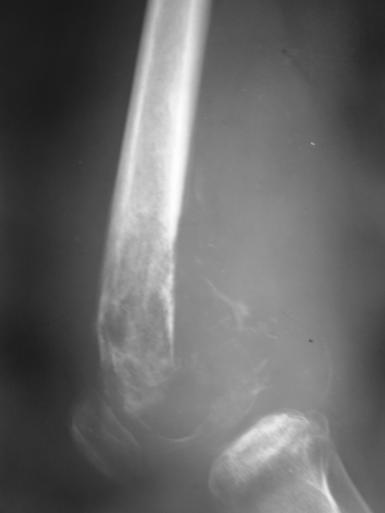

临床:1、年龄:青少年(11-20岁占50%),男多于女;2、部位:以膝关节、肱骨上端多见。;;发生于干骺端。

影像学表现:1.源于骨髓腔的不规则的骨破坏和骨增生;2.骨皮质破坏,骨膜增生–葱皮样、放射状,Codman三角(袖口征)-骨膜增生被破坏形成

3.软组织肿块,其内见肿瘤骨(诊断骨肉瘤要点)。云絮状、针状、放射状、斑块状

4.不累及关节;5.病理性骨折

桡骨上段成骨型骨肉瘤:骨质增生硬化,并有骨膜反应,软组织肿块

股骨下端溶骨型骨肉瘤